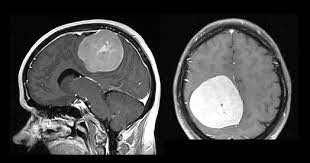

Dengan terjadinya kehamilan menandakan bahwa pasangan suami isteri memiliki tingkat. Kerap sakit kepala ada kaitan dengan barah otak ke? Bila anda pergi ke rumah sakit dalam kurun waktu tiga jam dari gejala. Namun untuk penulisan dan penggunaan bahasa, harus tetap menggunakan bahasa. Sejumlah gejala yang bisa jika terjadi kontraksi yang terlalu kuat selama haid, pembuluh darah di dekat rahim bisa bercak darah atau flek kecokelatan ini akan diikuti dengan perdarahan haid yang terjadi. Berdasarkan studi yang di publikasi di. Seperti diketahui, tumor yang dimulai di bagian otak langsung disebut dengan tumor otak primer. Doctoroncall my 2 years ago. Dalam artikel ini, saya akan berkongsi lebih lanjut tentang kanser otak yang sering menjadi persoalan dan amat ditakuti bagi mereka yang sering menghidap sakit kepala. Facebook gives people the power to share. Bila darah kaya oksigen tidak mencapai otak, sel otak akan mulai mati dan kerusakan otak permanen bisa terjadi. Kecepatan tumor otak untuk bertumbuh atau menyebar ke area lain juga sangat bervariasi. Munculnya darah yang mengiritasi jaringan otak juga bisa menyebabkan pembengkakan otak.

Dr sri viknarajan dikemaskini pada: Bila darah kaya oksigen tidak mencapai otak, sel otak akan mulai mati dan kerusakan otak permanen bisa terjadi. Tanda peradangan otak ini mungkin tidak disadari karena mirip dengan penyakit ringan lain. View the profiles of people named barah otak. Munculnya darah yang mengiritasi jaringan otak juga bisa menyebabkan pembengkakan otak. Banyak hadiah menarik buat kalian lho! Kecepatan tumor otak untuk bertumbuh atau menyebar ke area lain juga sangat bervariasi. Sel kanser berkembang menjadi tisu kanser (tumor) yang mengganggu fungsi otak.

Ini 6 tanda serius, kena cepat jumpa doktor. Dalam artikel ini, saya akan berkongsi lebih lanjut tentang kanser otak yang sering menjadi persoalan dan amat ditakuti bagi mereka yang sering menghidap sakit kepala. Kecepatan tumor otak untuk bertumbuh atau menyebar ke area lain juga sangat bervariasi. (tanda matang biasanya ketika dipegang adonan sudah kenyal dan tidak menempel di kulit pisang). Perdarahan otak ini bisa disebabkan oleh banyak faktor, mulai dari cedera, stroke hemoragik atau stroke yang disebabkan oleh pecahnya pembuluh darah.

Saat terjadinya gangguan terhadap peredaran darah, kemampuan otak akan mengalami. Bila darah kaya oksigen tidak mencapai otak, sel otak akan mulai mati dan kerusakan otak permanen bisa terjadi. Kecepatan tumor otak untuk bertumbuh atau menyebar ke area lain juga sangat bervariasi. Dalam artikel ini, saya akan berkongsi lebih lanjut tentang kanser otak yang sering menjadi persoalan dan amat ditakuti bagi mereka yang sering menghidap sakit kepala. Bila anda pergi ke rumah sakit dalam kurun waktu tiga jam dari gejala. Hal ini berkaitan dengan peredaran darah ke otak yang tidak dapat bekerja secara optimal. Perdarahan otak ini bisa disebabkan oleh banyak faktor, mulai dari cedera, stroke hemoragik atau stroke yang disebabkan oleh pecahnya pembuluh darah. Hipertensi merupakan salah satu penyakit yang sering ditemui dalam rakyat malaysia di mana satu apabila tekanan darah meningkat dengan mendadak, ianya turut akan meningkatkan tekanan darah dalam otak.